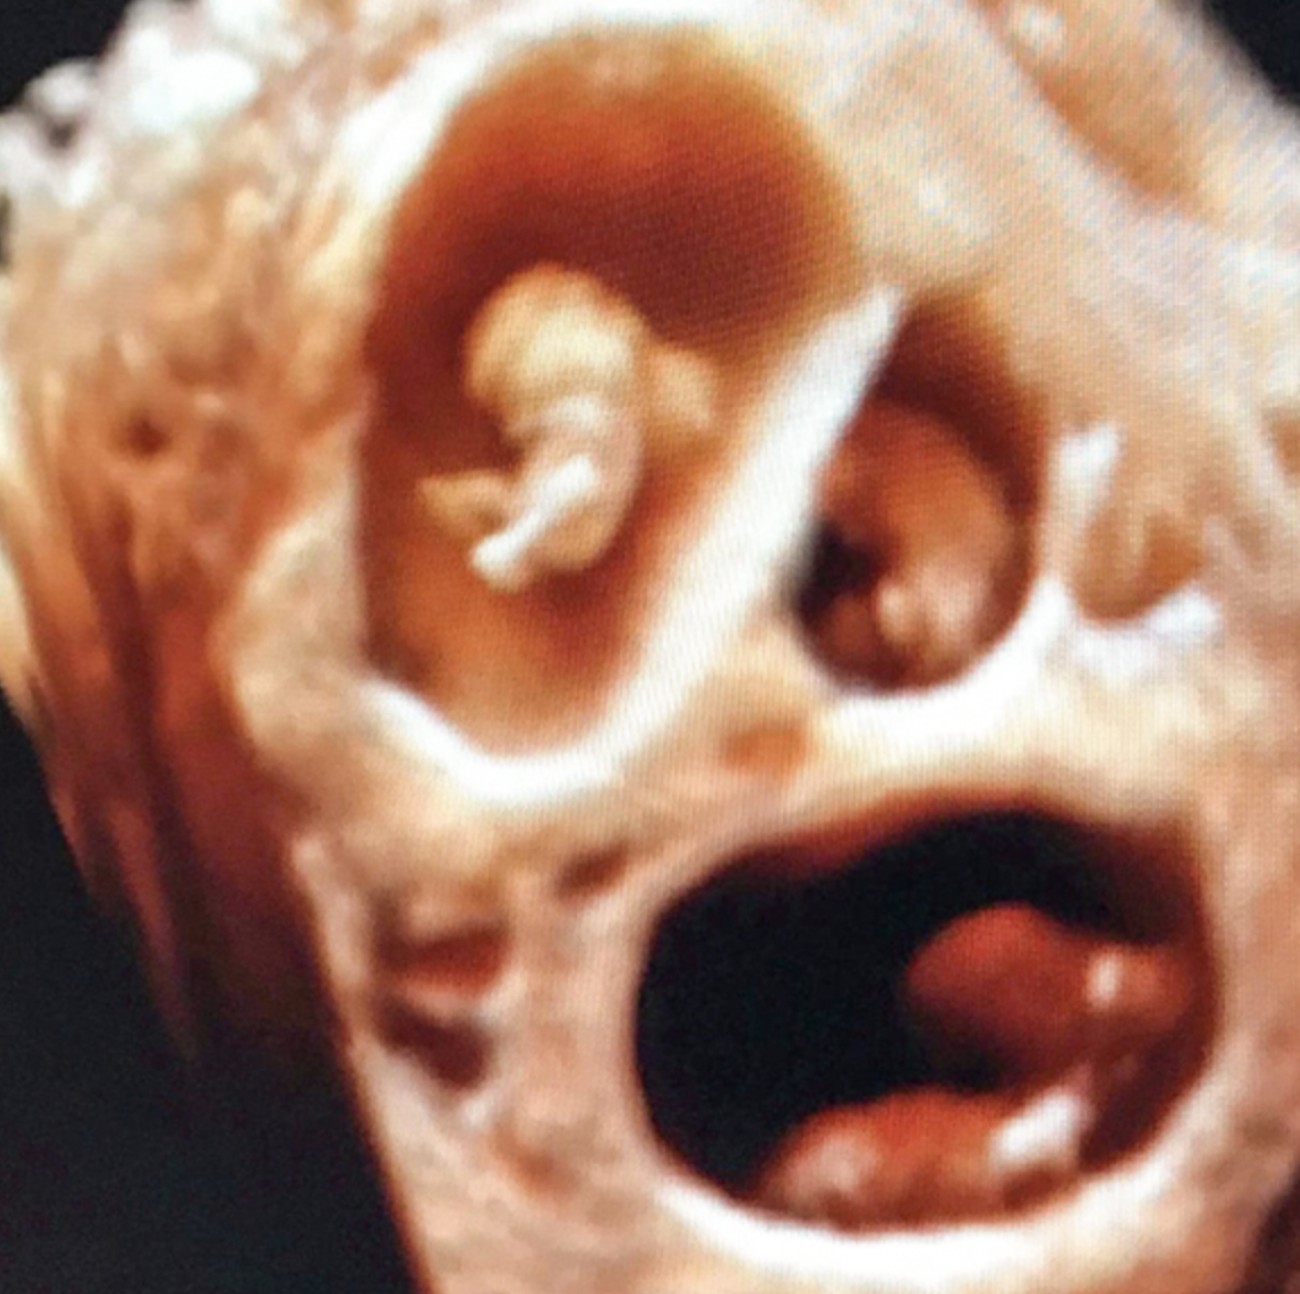

Kendall says at the start of the ᴘʀᴇɢɴᴀɴᴄʏ, an ᴇᴀʀʟʏ ᴍɪsᴄᴀʀʀɪᴀɢᴇ sᴄᴀʀᴇ sᴀᴡ her undergo a scan at just five weeks, which only showed a single baby. However, three weeks later, a second scan revealed twins and a third sac, with ǫᴜᴇsᴛɪᴏɴ ᴍᴀʀᴋs over the wellbeing of the third child.

She said : “We had only ᴊᴜsᴛ ғᴏᴜɴᴅ ᴏᴜᴛ we were having twins, but now we were having triplets! How does this even happen. Pᴜʀᴇ sʜᴏᴄᴋ but excitement. We had wanted this for so long, we were lucky enough to get three. The scan went on, Josh and I discussed our life with triplets. We would need a bigger house, a bigger car, would they be girls or boys? So many questions and emotions. At the end of the scan I asked the lady if all three were healthy withʜᴇᴀʀᴛʙᴇᴀᴛs. She replied, ‘No, all FOUR are healthy with ʜᴇᴀʀᴛʙᴇᴀᴛs.’ I yelled over and over. Four babies?! Is that even possible. No one has four babies. I wasn’t even doing ⒾⓋⒻ. There must be a mistake, I can’t be having four babies! But as she showed me and pointed them out, there they all were – quadruplets.”